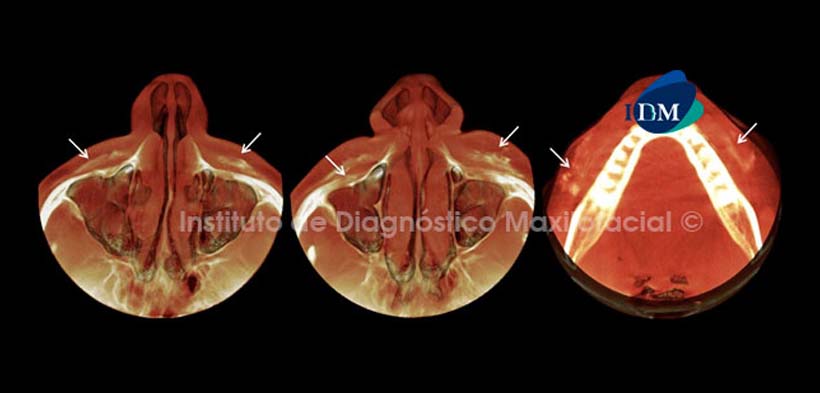

Así mismo, el software Romexis nos brinda diferentes opciones de reconstrucción 3D, como por ejemplo la opción para evaluar los tejidos blandos en la cual observamos las calcificaciones con un aspecto más difuso y confirmamos su disposición cefálico-caudal antes descrita (Fig. 3 y 4).

Otra de las alternativas de reconstrucción 3D es la opción MIP, en la cual se visualizan estas calcificaciones de manera más representativa y con aspectos nodulares, apreciando a la vez no solo la relación que tiene con los tejidos blandos sino también con los duros (Fig. 5).